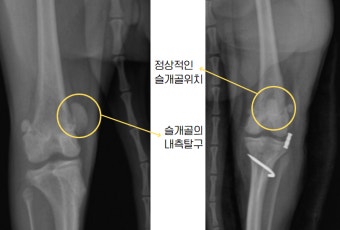

8. 슬개골 탈구 치료 방법

1~2등급의 경우에는 비수술적 요법(물리치료, 체중조절)도 가능합니다.

3~4등급이라면 대부분 수술을 권장해요. 관절을 제자리에 고정하고 연골 손상을 줄이기 위해서죠.